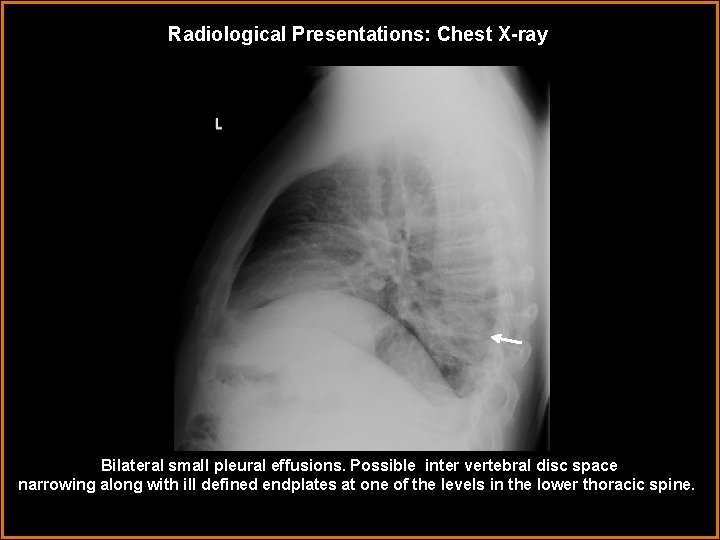

Radiological Presentations: Chest X-ray Bilateral small pleural effusions. Possible inter vertebral disc space narrowing along with ill defined endplates at one of the levels in the lower thoracic spine.

Findings and Differentials Findings: Chest radiograph demonstrates small bilateral pleural effusions with possible intervertebral disc space narrowing and illdefined endplates at one of the levels in the lower thoracic spine. A focal bulge at the lower left para spinal stripe is also visualized which is subtle. CT demonstrates T 8 -9 opposing endplate irregularity and erosive changes with mild pre- and paravertebral soft tissue swelling. MRI findings reveal altered marrow signal with enhancement of T 8 -T 9 vertebrae. Differentials: • Degenerative changes • Osteomyelitis • Vertebral body neoplasm